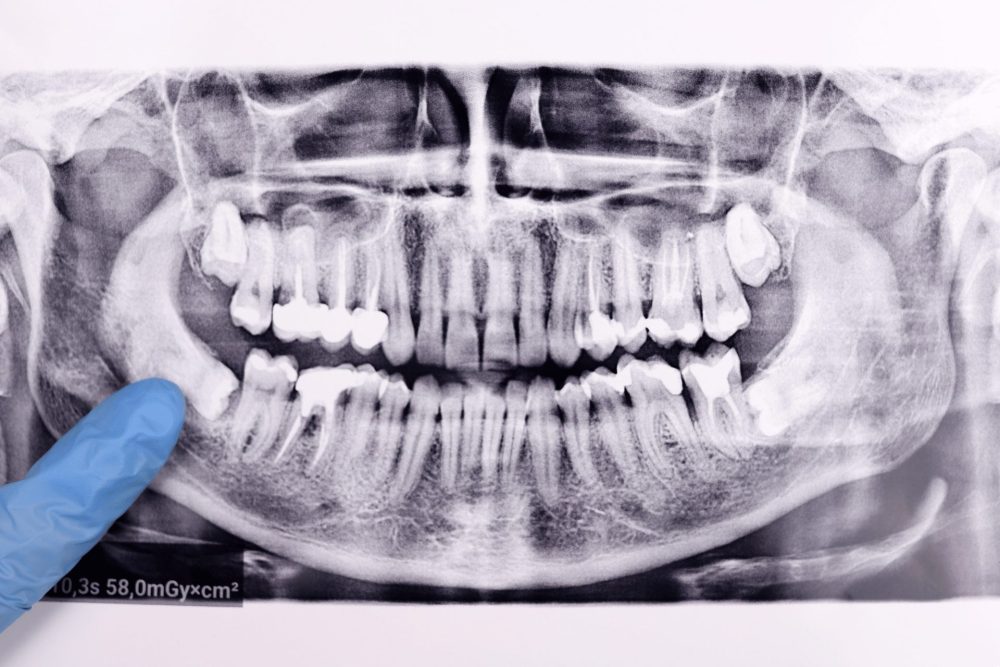

半年~1年に一度はレントゲンで状態を確認し、変化がないかを見守っていきましょう。

定期検診でレントゲンを撮り、状態を確認しておくと安心です。

まずは、歯科医院でレントゲンを撮り、自分の親知らずの状態を確認してみましょう。